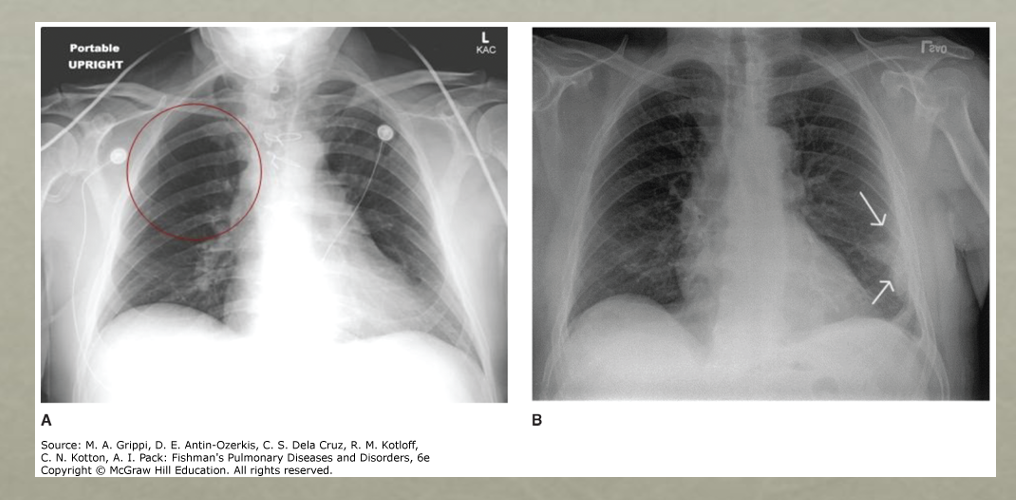

Pleural effusion

Very large pleural effusions may behave like a mass and produce a shift of the mobile mediastinal structures (i.e., the heart) away from the side of the effusion

Q

This is a pleural effusion

Notice the L side has the pleural effusion and the trachea is deviated the the R (because things are deviated away from the side w/ the pleural effusion)